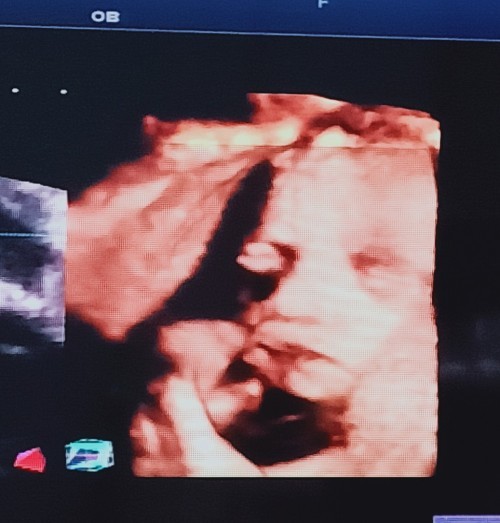

30 วีค ค่ะ 🥰

Post reply image